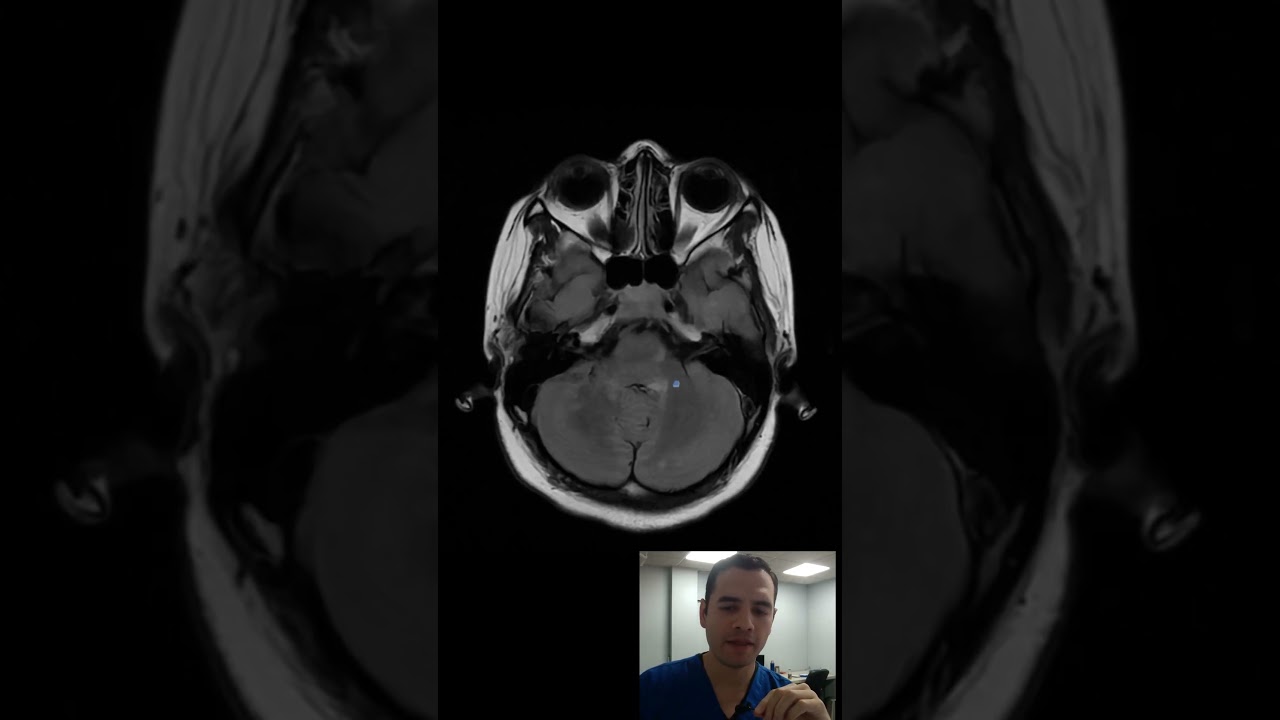

Tipos de Lesiones en Resonancia Magnética

Las resonancias magnéticas en pacientes con esclerosis múltiple pueden revelar diferentes tipos de lesiones, que se clasifican generalmente en lesiones activas y pasivas.

Lesiones activas

Las lesiones activas son áreas donde se ha producido una reciente desmielinización, y suelen aparecer como manchas brillantes en las imágenes de RM. Estas lesiones indican inflamación y son a menudo el resultado de un brote de la enfermedad.

Características: En la RM con gadolinio, estas lesiones se realzan, lo que indica que están activas y en proceso de inflamación.

Importancia clínica: La presencia de lesiones activas puede correlacionarse con la aparición de nuevos síntomas o la exacerbación de los existentes.

Lesiones inactivas

Las lesiones inactivas, por otro lado, son áreas donde ha habido desmielinización, pero que ya no muestran actividad inflamatoria. Estas lesiones aparecen como áreas más oscuras en las imágenes de RM.

Características: Estas lesiones no se realzan con gadolinio, indicando que no hay inflamación activa.

Relevancia: Aunque no están asociadas a actividad reciente, su presencia puede indicar daño cerebral acumulativo y potencial progresión de la discapacidad.

Características de las imágenes

Las imágenes de RM se pueden clasificar en diferentes tipos según el protocolo utilizado:

RM T1: Proporciona imágenes anatómicas y ayuda a identificar lesiones antiguas.

RM T2: Resalta las lesiones activas y pasivas, siendo útil para evaluar la carga de la enfermedad.

RM con gadolinio: Permite visualizar lesiones activas mediante el realce de contraste.